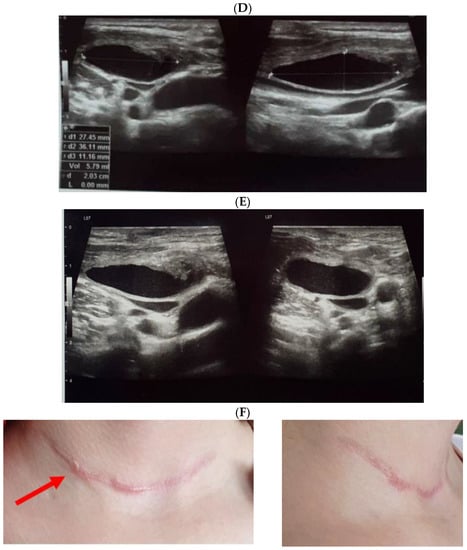

Ultrasound—guided fine need aspiration of the right mass provided cvasi-complete reduction of the liquid with stationary ultrasound features after 90 min. The liquid examination showed mature lymphocytes, rare erythrocytes, rare cholesterol crystals, lymph fluid, consistent with the diagnostic of lymphocele. A mild clinical improvement of HS—associated features was registered, but within 2 days, the neck mass rapidly regrew, and the patient was re-admitted. Under local anesthesia, there was a liquid evacuation (macroscopic aspect with milky-like aspect, a volume of 5–6 mL) and a drain tube was placed for 4 days. Ultrasound aspects showed a progressive regression of the right cystic mass with improvement of HS which slowly remitted within the next 2–3 months. (Figure 4).

Figure 4.

The evolution of within following weeks after thyroid surgery ultrasound features. (A). Right neck ultrasound aspect at the moment of fine needle aspiration (5 weeks since surgery)—on the right and 6 days after fine needle aspiration procedure (after cvasi-complete evacuation, the cystic mass relapsed within 48 h)—on the left. (B). Right neck ultrasound within the first day of tube drainage (6 weeks since initial surgery) showing a massive reduction of the cystic mass. (C). Drainage tube was removed after 4 days. Post-thyroidectomy scar and post-tube removal aspect. (D). Right neck ultrasound after 2 weeks from removing the drainage—persistent cystic mass, but with progressive improvement of HS (approximately 9 weeks since initial surgery). (E). Right neck ultrasound after another 2 weeks from removing the drainage –progressive reduction of cystic mass, but with remarkable improvement of HS (approximately 11 weeks since initial surgery). (F). Scar aspect 12 weeks since surgery and 5 weeks since lymphocele drainage. (G). Recovery of HS—approximately 8 weeks since drainage. (H1,H2). Bilateral neck ultrasound 20 weeks since thyroid surgery showing regression of the lesions on both sides versus prior examinations. (H1). Right later-cervical cystic collection of 2 by 2.8 by 0.9 cm (2.5 mL) and peripheral areas of fibrotic reorganization. (H2). Left later-cervical hypoechoic, inhomogeneous mass (no vascular signal) showing fibrotic reorganization (0.25 mL).

Despite full recovery, intermittent episodes of nasal obstruction/congestion (which were never registered pre-operatory) persisted for one year. The patient remained under life time protocol of surveillance for MEN2.